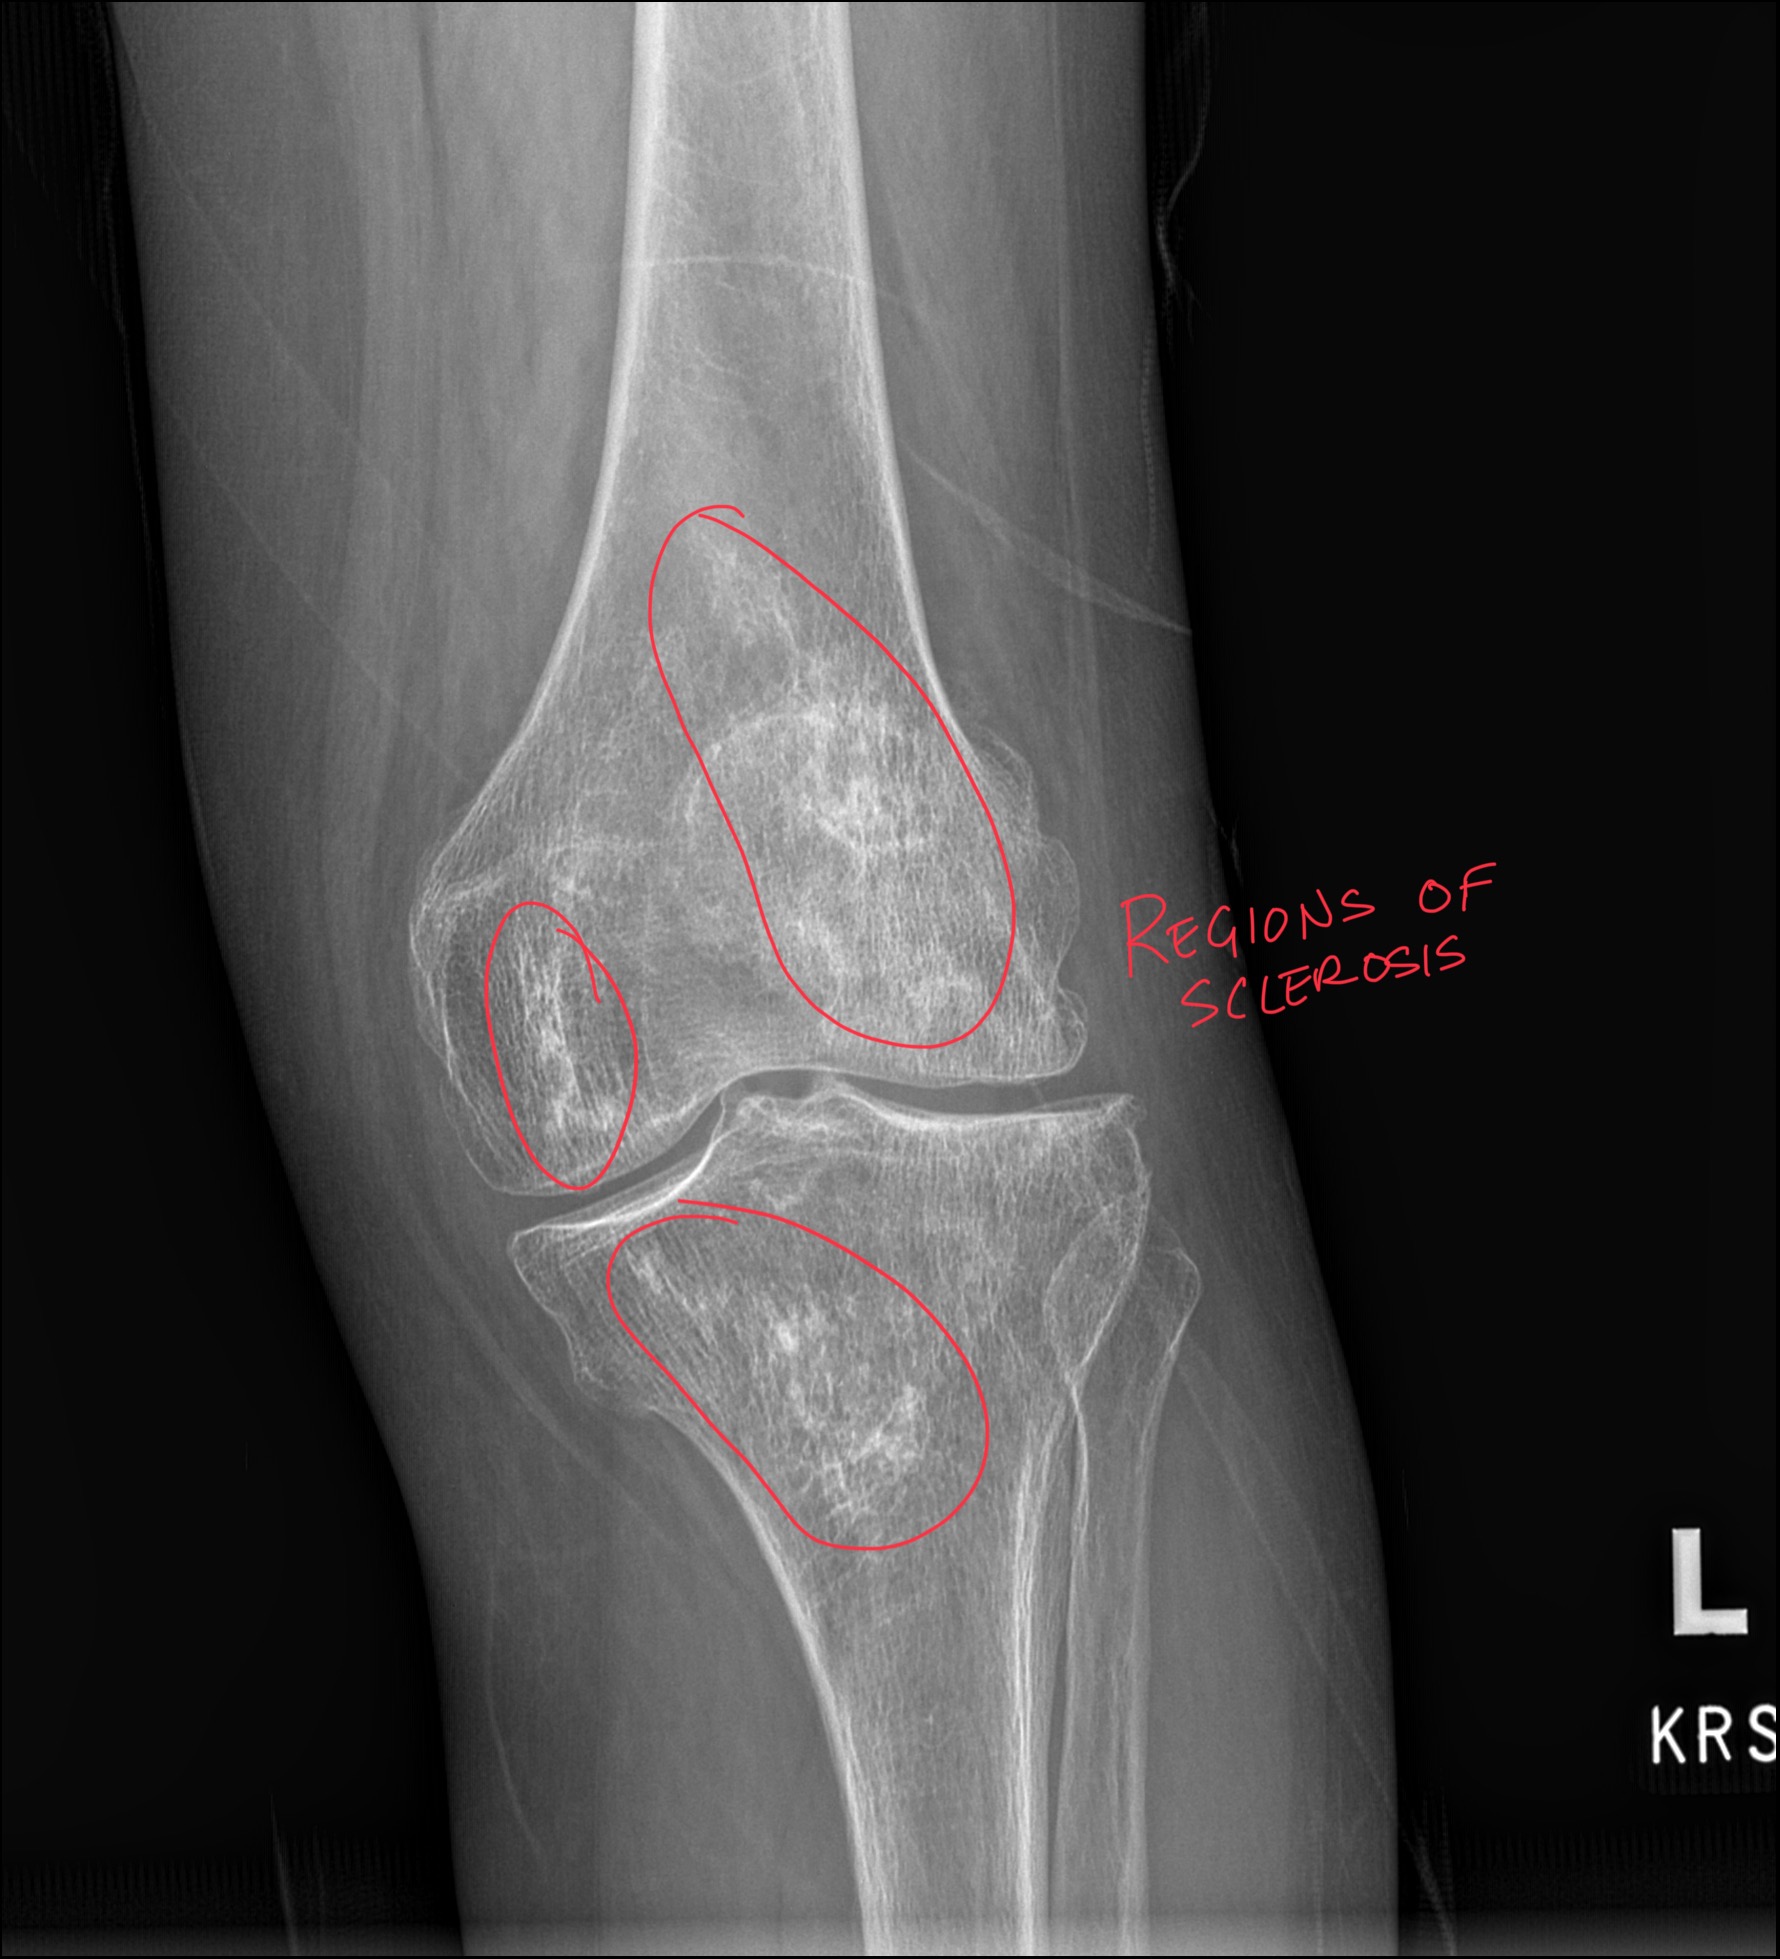

Pellegrini Stieda Annotated Kinetic Radiology

Pellegrini-Stieda Lesion: When Medial Knee Pain Hides in Plain Sight

Clinical Presentation This presentation is one that clinicians across chiropractic and primary care encounter regularly. Medial knee pain in a

Read More